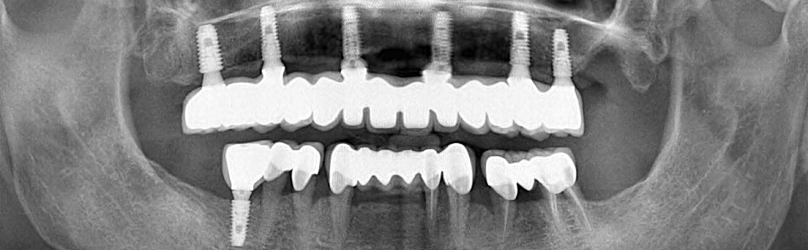

La première étape du processus de traitement consiste à prendre des images radiographiques détaillées. Ces images aident à déterminer le plan de traitement le plus approprié en évaluant la structure de votre mâchoire et votre santé dentaire. Nos radiographies révèlent à quel point le processus de traitement est extrêmement minutieux.

Dans les étapes ultérieures, vous pouvez regarder des vidéos sur la façon de placer des implants et de produire des prothèses. Ces vidéos visent à fournir une perspective informative à nos patients en montrant chaque étape du processus. Chaque étape est réalisée minutieusement par nos médecins experts.

Une fois le traitement terminé, vous pourrez visionner nos entretiens avec nos patients et entendre leurs expériences. Ces entretiens, qui racontent comment leur qualité de vie s’est améliorée en peu de temps et la valeur ajoutée du traitement implantaire à leur santé, seront une source d’inspiration pour nos autres patients.